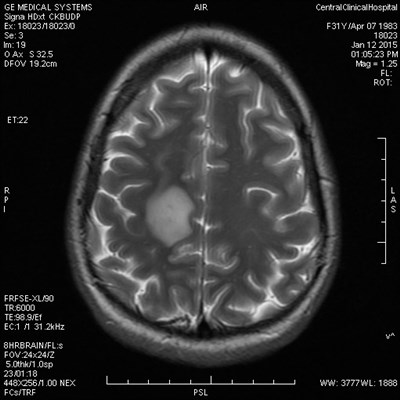

Демиелинизирующие заболевания мозга: МРТ изображения